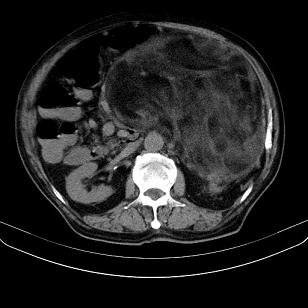

标题: CT21671:男,88岁,左上腹包块 [打印本页]

标题: CT21671:男,88岁,左上腹包块

患者因咳嗽而住院,自觉右上腹包块,无其他不适。

另肠腔扩张及液平,肠梗阻?

考虑腹膜后脂肪肉瘤可能性大。 畸胎瘤不除外。